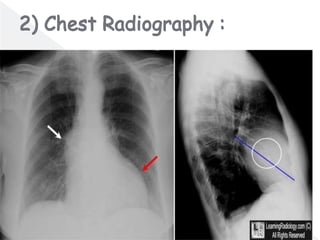

๏‚ž Diagnostic studies in the emergency

department should include:

โ€บ electrocardiography (ECG),

โ€บ chest radiography .